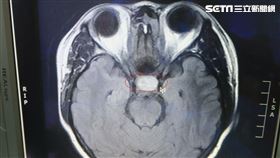

頭痛雙眼視力急速退化 竟是腫瘤侵腦

一名60歲的廖先生,過去幾年內常有頭痛的症狀,今年年...